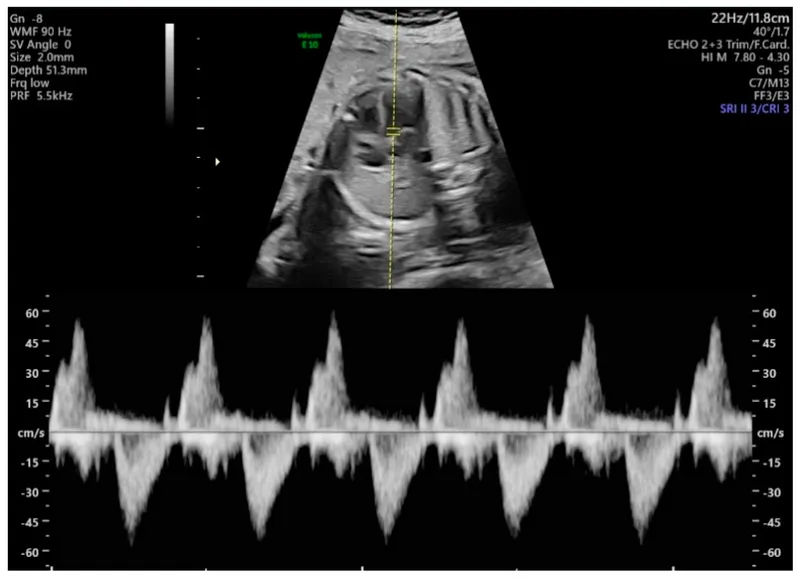

- Doppler US:

- Umbilical Artery (UA): ↑S/D ratio, PI, RI → placental insufficiency.

- Middle Cerebral Artery (MCA): ↓PI → brain sparing (fetal hypoxia).

- Ductus Venosus (DV): Abnormal 'a' wave → severe compromise.

⭐ In Umbilical Artery Doppler, Absent or Reversed End-Diastolic Flow (AREDF) indicates severe fetal compromise.

- Doppler (UA, MCA): Assesses fetal well-being, IUGR, and hypoxia.